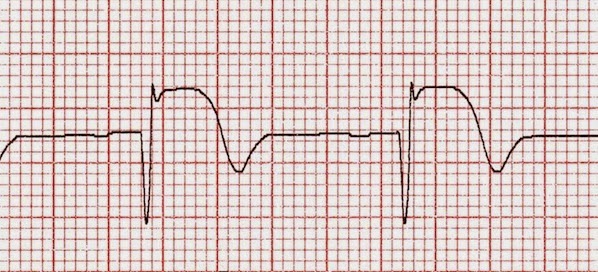

En entornos donde la reperfusión mecánica primaria no es accesible, el uso de fibrinolíticos sigue siendo la mejor opción en el infarto de miocardio con ST elevado. Esta revisión compara la eficacia y seguridad de las alternativas disponibles. The Lancet, 19 de agosto de 2017